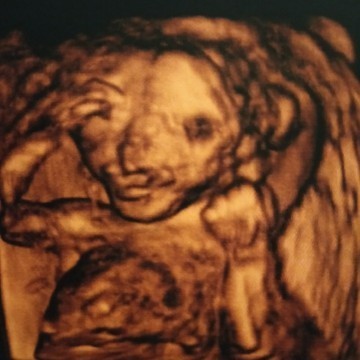

ขอเสียงคุณแม่เดือน มกราคม จ้า แม่บ้านนี้ได้ ผู้ชาย🤰🤰🤰👪

16 มกราคม บ้านนี้ได้ผู้หญิงจ้า😁

22 มกราคม 64 จ้า คุณหมอบอก 60% ได้ผู้ชาย🤰

ผู้ชายเหมือนกันคะ..ทีมมกราคม